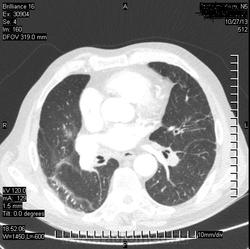

Коллега, а что, инфаркт искали? Или у Вас так окклюзии ЛА ищут? Интересно, а просто ОГК , для искл. пневмонии

( или инфаркт-пневмонии) слева?

Виноват. Не все вчера успел выложить.ТЭЛА.

Всё понятно стало. А, вот мне, как-то не очень легочная вена слева... Там все нормально? Или тоже тромб?

ТЭЛА слева, я правильно вижу?

Да. Слева.

Я не маститый "КТ-шник". На дежурствах в 2-3 часа ночи главное ухватить суть (на мой взгляд). Может быть тромб.